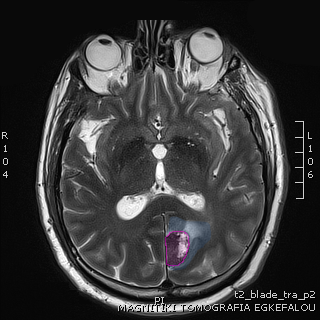

Όγκος εγκεφάλου με περιβάλλον οίδημα. |